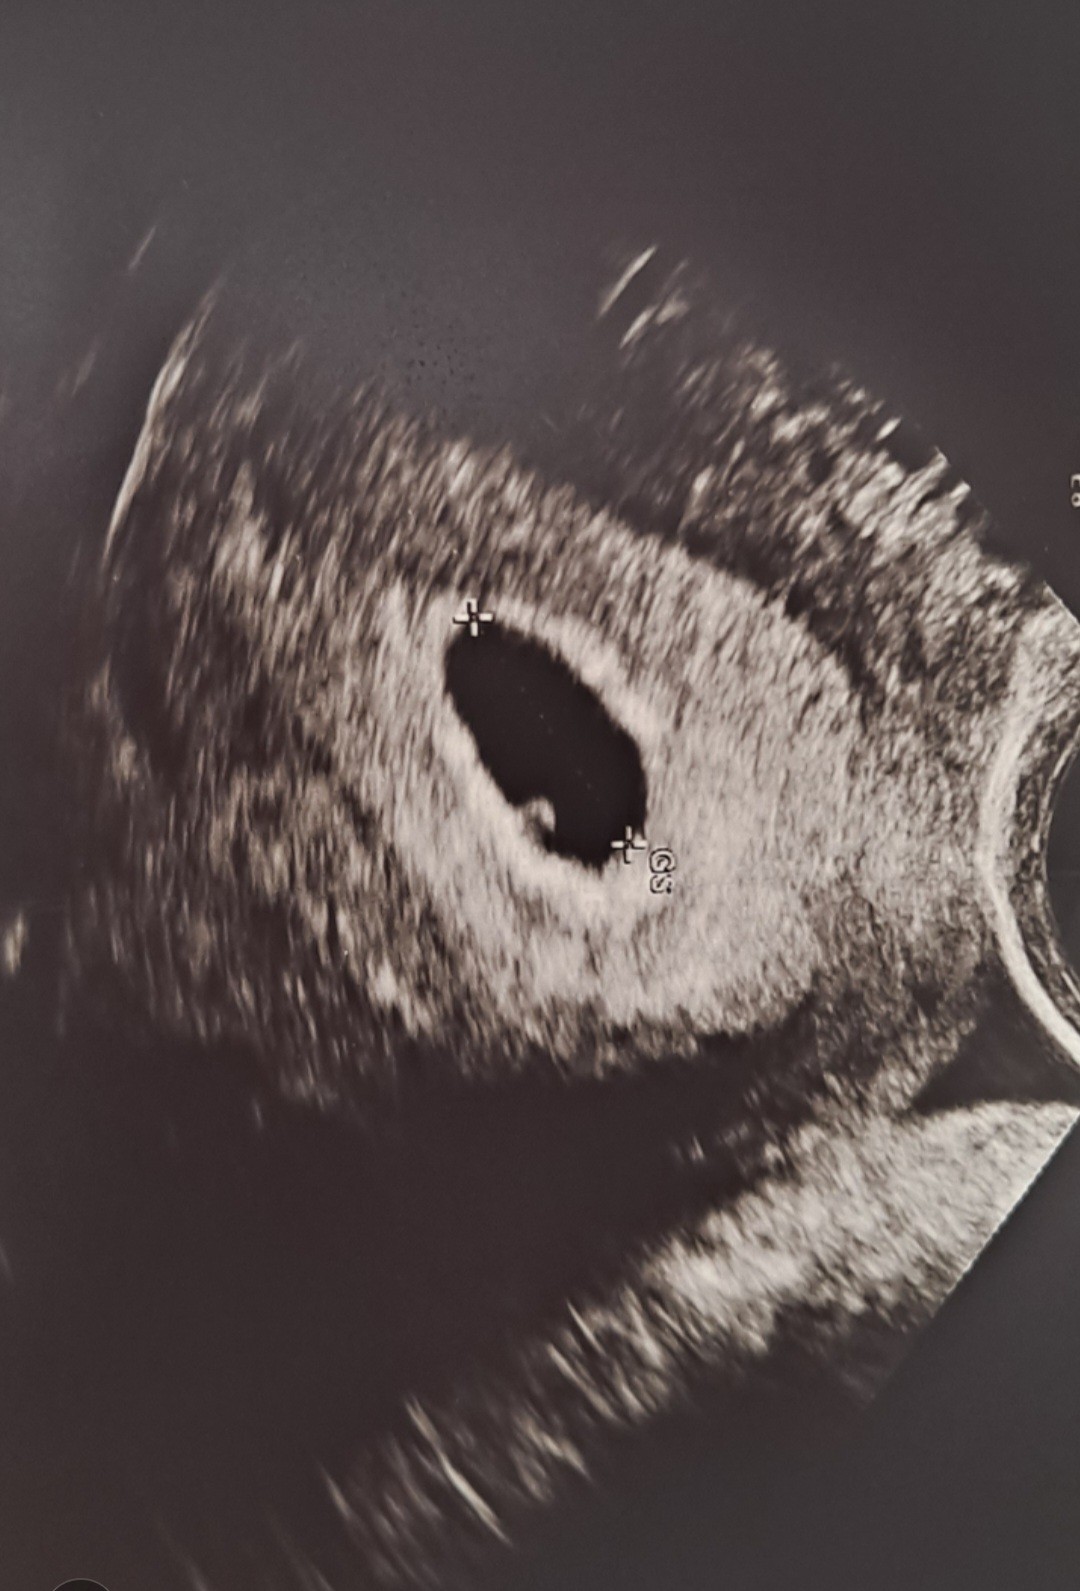

Moja malutka fasolka ❤❤❤

Załączniki

• Screenshot_20220829-184607_Gallery.jpg

Screenshot_20220829-184607_Gallery.jpg

243,1 KB · Wyświetleń: 87